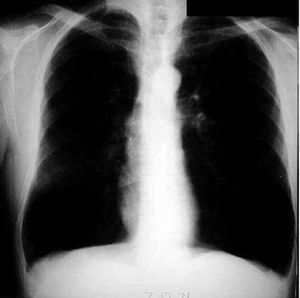

Chest x ray PA view showing hyper translucent both lung field, tubular shaped heart, low flat diaphragm. So my radiological diagnosis is emphysema.